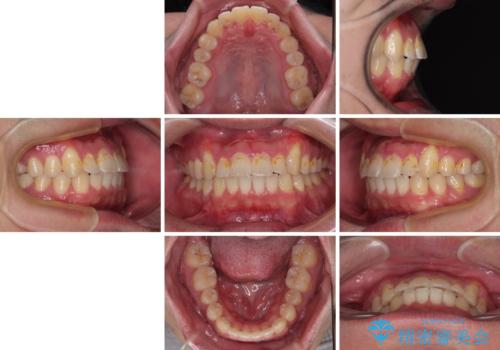

舌突出癖が改善されず、なかなか正中の隙間や上下の前歯が接触しなかったために治療が長期化してしまいました。

また、治療期間中のプラークコントロールが悪く、ブラッシング指導も奏功しなかったため、装置の周りが脱灰した状態(初期むし歯)となってしまいました。